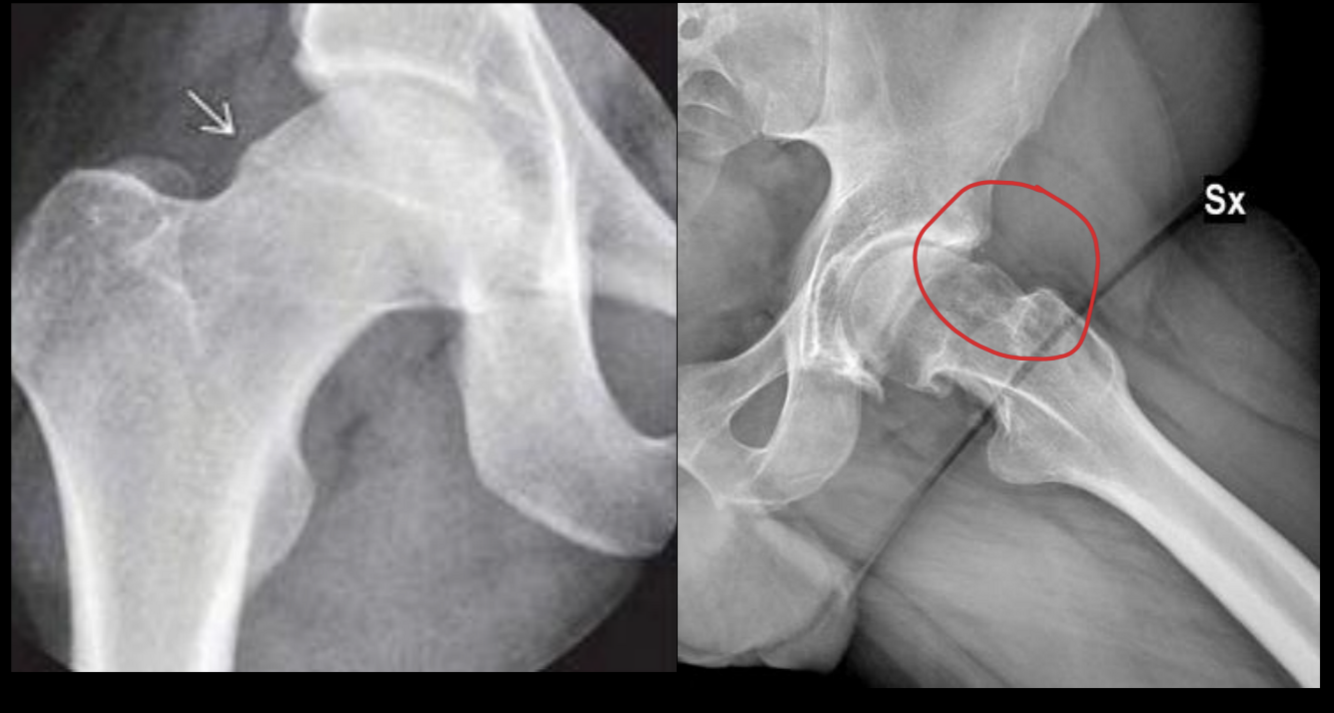

CAM: deformidad cuello femoral

PINCER: sobrecobertura del acetabulo

CAM: + en hombres jovenes

PINCER: mujeres

CAM

PINCER